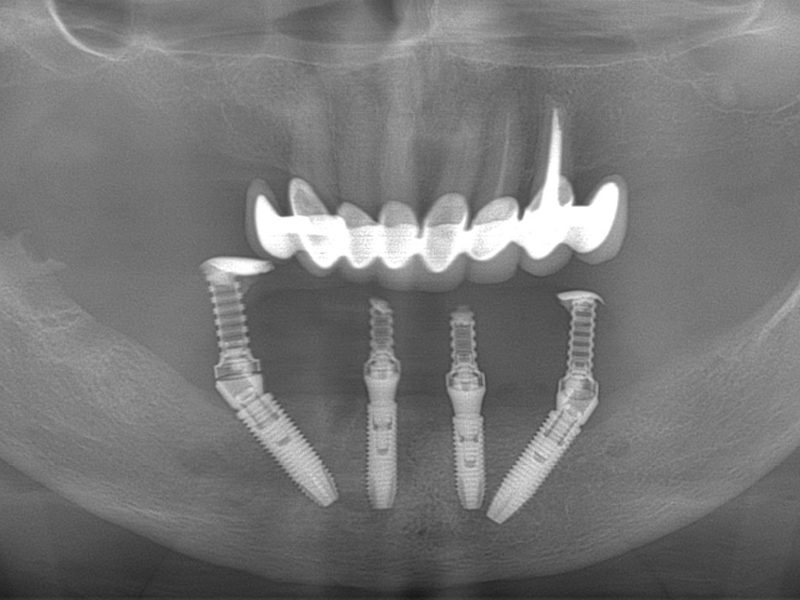

Using the All-On – 4 method; Dental implants are inserted in the same day and in a few hours, a temporary but fixed prosthetic job is performed immediately which will remain until the implants are perfectly integrated into the bone. After about 4-6 months, definitive prosthetic rehabilitation will be performed, which will be screwed onto existing implants. The screw fixing will allow you to remove the restoration (fixed bridge) when necessary.

The specificity of this procedure is that the teeth are fixed on four implants. Thanks to the particular method of inserting the implants, bone reconstruction is not necessary, which is instead a requirement when it is necessary to reconstruct in patients who have total tooth loss.